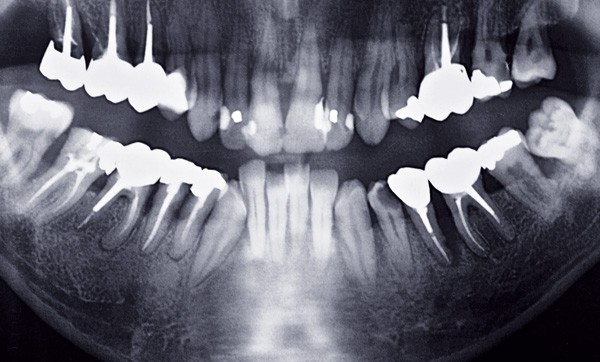

Le patient a fait l’objet à l’époque d’un bilan dentaire sous la forme d’un cliché panoramique (OPT) (fig. 1). Il présentait alors 14 dents au maxillaire (absence de 18 et 25), et une arcade complète à la mandibule.

– 17, 16, 15 : présentent des restaurations par couronnes coulées (métal non précieux), avec des inlays core sous-jacents ;

– 14 : obturation coronaire volumineuse sans obturation radiculaire visible ;

– 13 : lésion carieuse mésiale, peu évoluée ;

– 12 : obturations proximales ;

– 11 et 21 : obturations distales et petites lésions carieuses du côté mésial ;

– 22 : obturations proximales et palatines ;

– 23 : dent indemne ;

– 25 obturation occluso-distale sur dent probablement vitale ;

– 26 : dent couronnée, inlay core sous-jacent ;

– 27 : obturation occluso-mésiale et lésion carieuse distale évolutive ;

– 28 : dent indemne de carie.

Côté droit : on note une poche parodontale entre 17 et 16, atteignant les deux tiers de la hauteur radiculaire des dents (supérieure à 5 mm), une poche plus modérée entre 16 et 15, une atteinte parodontale au niveau 11 et 12 (plus avancée sur la 12).

Côté gauche : au niveau de la dent 28 :

– une atteinte dépassant la moitié de la hauteur radiculaire. De plus, la dent possède une racine conique et devait présenter une mobilité ;